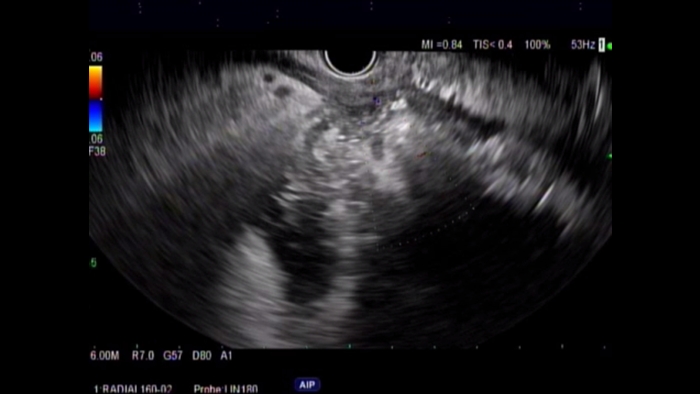

EUS with Doppler revealed a large wall of necrosis measuring 20cm. The lesion had a thick wall and contained solid debris with copious amounts of liquid, common for WON with liquefaction.​

A CT scan was performed six weeks later showing WON formation with liquefaction, as well as good apposition to the posterior wall of the stomach. The patient was referred for EUS-guided transluminal AXIOS™ Lumen Apposing Metal Stent (LAMS) placement/cyst gastrostomy.​